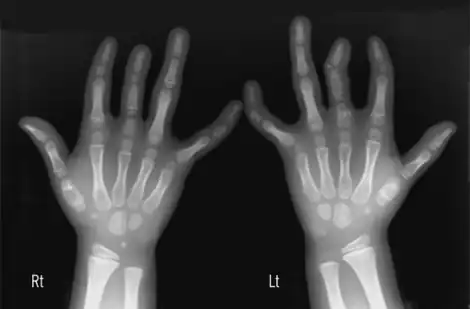

X-ray Brachydactyly type C (see below)

Type C, BDC 113100 GDF5 20q11.2 Brachydactyly type C or Brachydactyly Haws type.